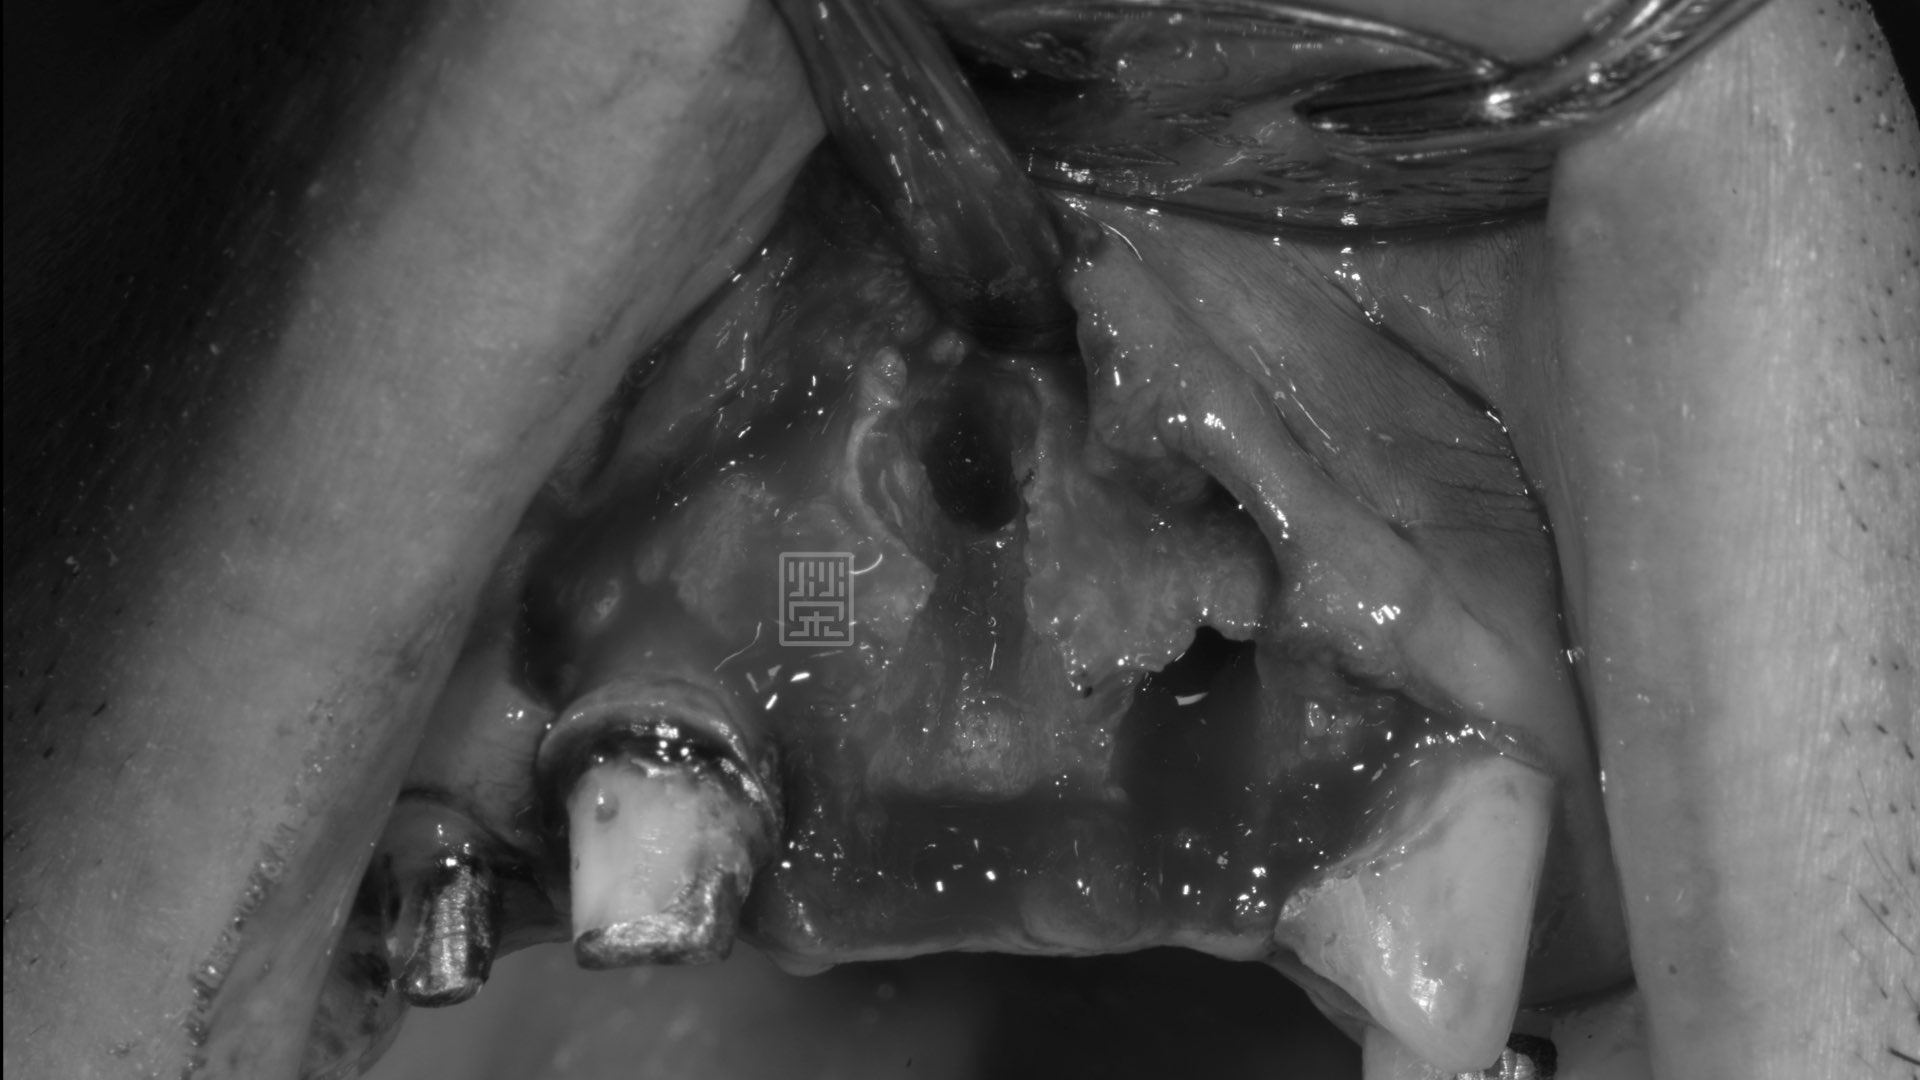

牙根拔除後,發現斷裂處骨頭嚴重缺損

再生醫材補骨